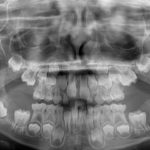

Cisti eruttive multiple in un bambino di 7 anni. Caso clinico